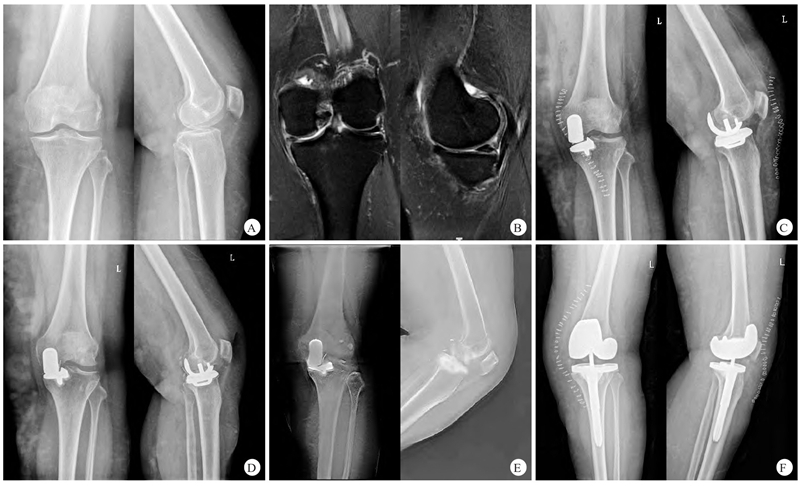

典型病例:图2 患者,女,60岁,左膝单间室骨关节炎,行活动平台UKA

A.术前左膝正、侧位X线片显示内侧间隙变窄;B.术前左膝MRI提示左膝关节退行性病变,内侧软骨磨损;C.术后1周左膝正、侧位X线片显示假体位置良好;D.术后12个月后因外伤摔倒后出现左膝关节疼痛,左膝正、侧位X线片可见衬垫向后外方脱位;E.术后12个月左膝矢状位及冠状位数字化体层融合成像提示衬垫向后外方脱位;F.全膝关节置换翻修术后2周左膝正、侧位X线片显示假体位置良好